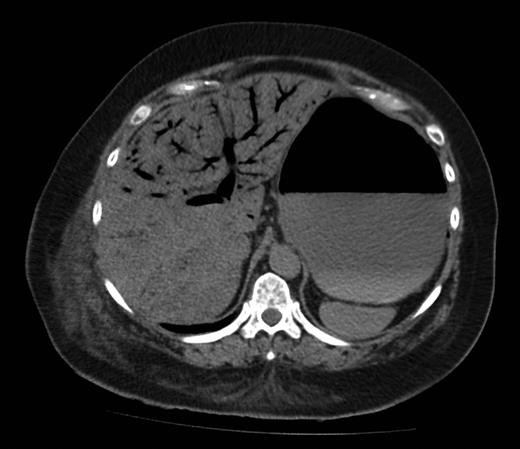

Figure 1 shows a remarkable amount of air in the hepatic portal venous system. Figure 2 demonstrates how the portal vein, splenic vein, superior mesenteric vein and its branches were all outlined with air. Figure 3 shows air within the wall of both small and large bowels. Overall, the radiological findings were suggestive of extensive bowel ischaemia.

Axial image demonstrating intra-mural gas affecting both small and large bowels.